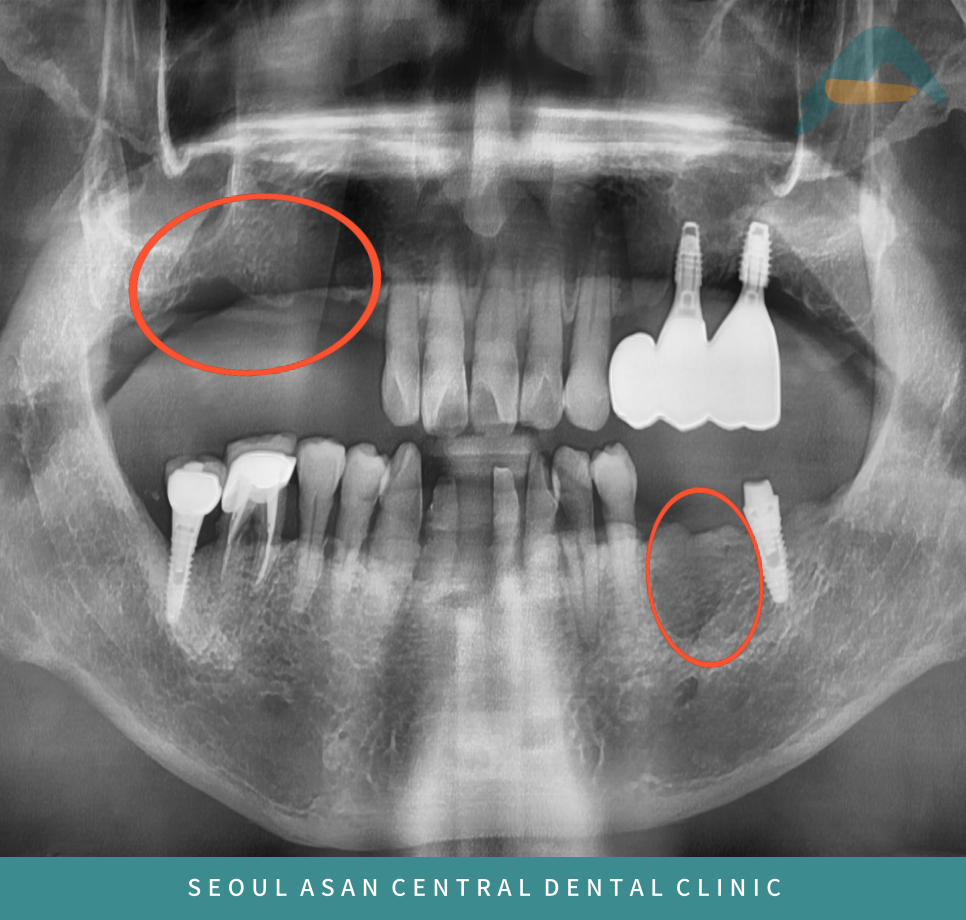

환자분께서는 위턱 오른쪽과

아래턱 왼쪽 잇몸뼈가 부족하여

임플란트가 어려워 성남치과

위턱 오른쪽 어금니 부위는

상악동이 내려와 있어

임플란트 식립을 위해서는

상악동 거상술이 필요하고

사진상에서 까맣게 보이는 것처럼

뼈가 많이 녹아 약해져 있다면

뼈이식을 동반하여

임플란트 식립이 필요할 수 있습니다.